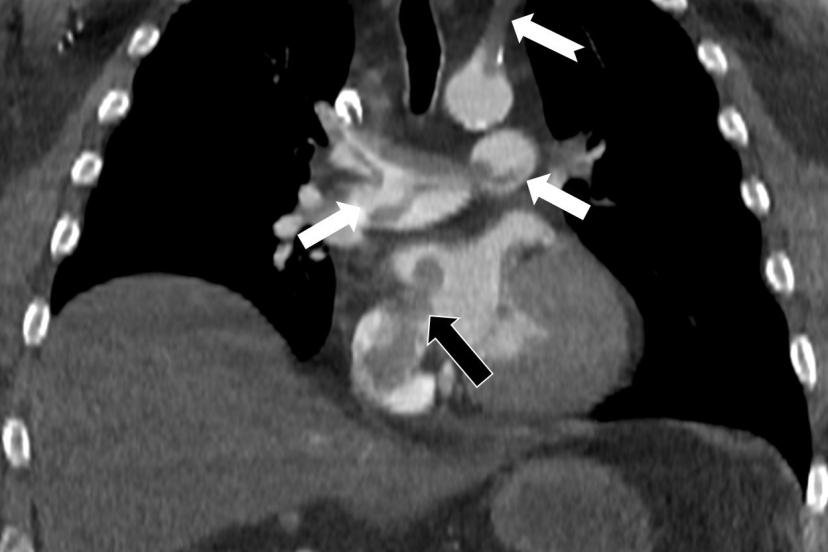

Kalp ve akciğer görüntülemesi alanındaki uluslararası bilimsel çalışmalarıyla tanınan Radyoloji Uzmanı Prof. Dr. Nevzat Karabulut, dünyanın önde gelen tıp dergilerinden Radiology dergisinin 2025 Kasım sayısında yayımlanan "Paradoxical Embolism with Clot-in-Transit in Atrial Septal Defect" adlı çalışmasında, penis ameliyatından 5 gün sonra ani göğüs ağrısı, nefes darlığı ve kol uyuşması şikâyetiyle hastaneye başvuran 60 yaşındaki bir hastada, daha önce fark edilmemiş kalp odacıkları arasındaki bir delikten geçen pıhtının hayati tehlike oluşturduğunu ortaya koydu.

Bir dönem Özel Denizli Tekden Hastanesi’nde de görev yapan Prof. Dr. Nevzat Karabulut’un yaptığı çalışmada; akciğerin bilgisayarlı tomografi anjiyografisi sayesinde toplar damarlardan kaynaklanan pıhtının akciğer damarlarını tıkaması yanında, kalpteki delik nedeniyle kalbin sağ tarafından sol tarafına geçerek ana atardamara ulaştığı ve sol kol damarını tıkadığı gösterildi.

Emboli görüntülemesi konusunda çok sayıda bilimsel çalışması bulunan Prof. Dr. Karabulut, genelde bacak damarlarından kaynaklanan pıhtıların ölümcül olabilen akciğer embolisine yol açması yanında, kalp deliği olan hastalarda ana atardamar yoluyla beyin, kol ve bacak gibi vücudun diğer bölgelerine de geçerek ani damar tıkanmasına (paradoks emboli) bağlı bulgulara yol açtığını belirtti. Prof. Dr. Karabulut’un çalışmasında nedeni bilinmeyen pıhtı atmalarında kalpteki gizli deliklerin mutlaka araştırılması gerektiği vurgulanarak ekokardiyografi ve bilgisayarlı tomografi tetkiklerinin erken ve doğru tanı koymada hayat kurtarıcı rolüne dikkat çekildi.